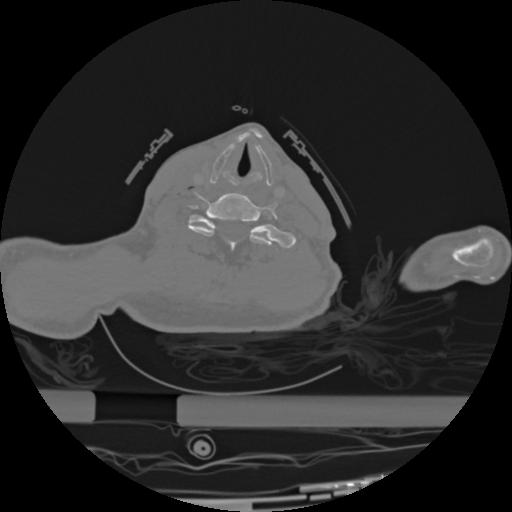

22 ANGIO,CE,Vol,0.5,ANGIO,,